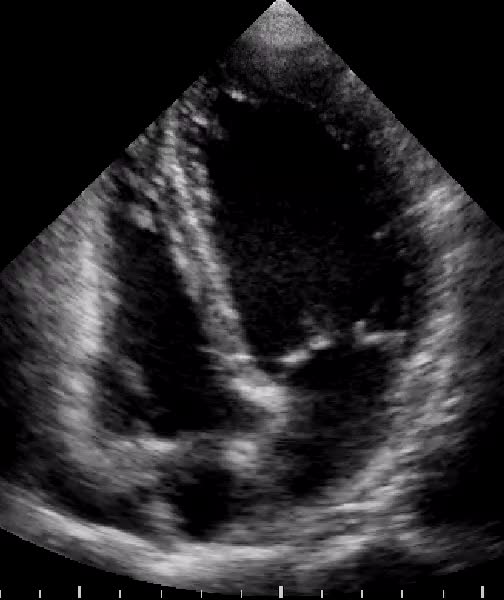

Miocardio non-compattato del ventricolo destro

Andrea Barbieri